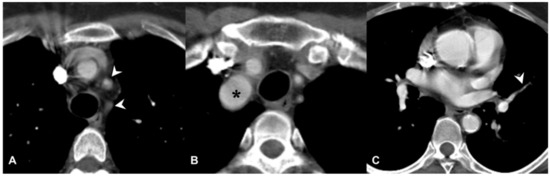

2.6. Takayasu Arteritis (TA)

| Takayasu arteritis | Stenosis and/or occlusion of segmental arteries; stenosis and/or occlusion of lobular or main pulmonary arteries (less common); C.E. of vessel wall may be evident |